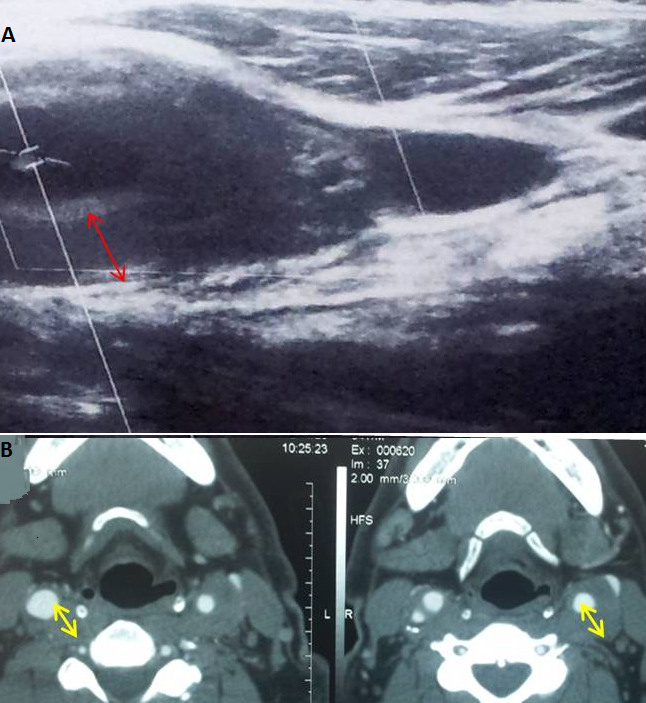

L'artérite de Takayasu (AT) est une panartérite inflammatoire rare de cause inconnue, touchant les artères de gros et de moyen calibre. Elle survient essentiellement chez la femme jeune. Sa survenue chez la population masculine est rarement rapportée. Un homme âgé de 54 ans était hospitalisé pour carotidodynie gauche associée à un amaigrissement de 18 kg en six mois. L'examen clinique était sans particularités. Il avait à la biologie une anémie à 10 g/dl, un syndrome inflammatoire et un bilan lipidique correct. L'echodoppler (A) et l'angioscanner (B) des troncs supra-aortiques objectivaient un épaississement étendu et fusiforme de l'artère carotide primitive gauche avec une sténose estimée à 60% de l'artère carotide interne droite. L'enquête infectieuse, le bilan immunologique et de thrombophilie étaient négatifs. Le diagnostic d'une AT a été retenu. Le patient a reçu une corticothérapie à la dose initiale de 1 mg/kg/j. L'évolution était favorable avec disparition des carotidodynies et régression du syndrome inflammatoire biologique.